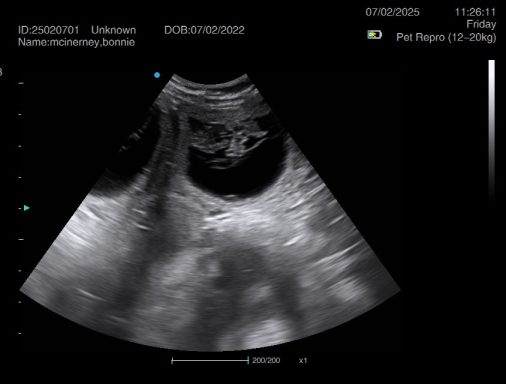

Ultrasound pregnancy scanning is a safe, non-invasive way to confirm pregnancy in dogs and cats, offering breeders and pet owners peace of mind and vital information to support responsible care. It allows us to detect gestational sacs, assess foetal development, and estimate litter size—all while ensuring the wellbeing of the animal.

Pregnancy can sometimes be detected as early as Day 18 post-mating, but scanning at this stage is not routinely recommended. Embryos are still developing and may not be clearly visible, and there is a natural risk of embryo resorption, which can lead to misleading or inconclusive results.

For the most accurate and reliable scan, we advise booking between Day 25 and Day 32, when pregnancy is more easily confirmed and foetal structures are clearer. If an early scan is performed and no pregnancy is detected, we offer a FREE complimentary re-scan after 7 days at the clinic to ensure clarity and support informed decision-making.

Our approach balances early insight with ethical care—always prioritizing the comfort of the animal and the accuracy of the results.